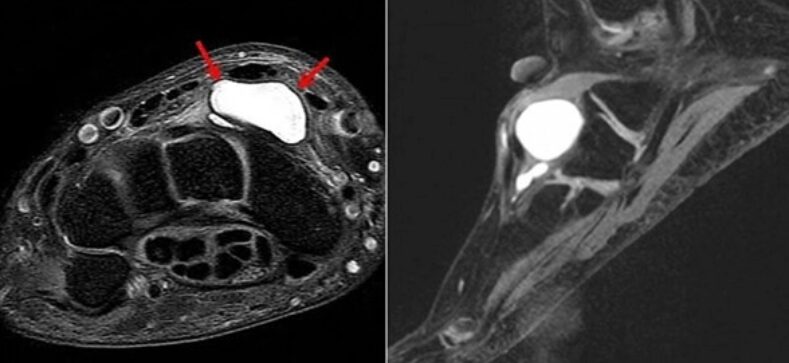

손목 결절종은 관절이나 힘줄을 감싸고 있는 조직에서 젤리 같은 점액 성분이 새어 나와 한곳에 고이면서 혹처럼 부풀어 오르는 질환입니다.

만져보면 말랑하거나 약간 단단한 느낌이 들며, 내부에는 투명한 점액이 차 있는 것이 특징입니다.